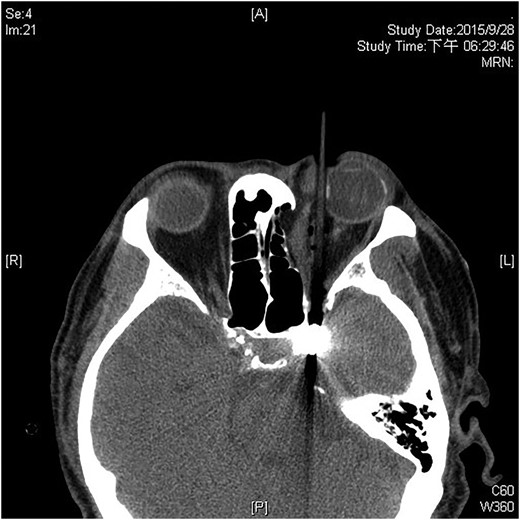

A 60-year-old man was admitted to our medical ward due to aspiration pneumonia. He had a medical history of diabetes mellitus, end-stage renal disease; a tuberculosis bacilli-related thoracic spine infection with paraplegia, and a previous coronary artery bypass graft. During his third day at the hospital, he obtained a ballpoint pen and inserted it into his left eye. On physical examination, the patient appeared to be alert with normal vital signs. The ballpoint pen protruded from his left upper eyelid; it was firmly lodged in his left medial orbit between the globe and nose, causing left eye proptosis (Fig. 1). Neurologic examinations revealed that the patient was neurologically intact except for complete left ophthalmoplegia. Brain CT scanning revealed a tubular foreign body that was located in the anteroposterior plane extending from the orbital apex and directly into the parasellar region (Fig. 2). The metallic portion of the foreign body was entrapped in left optic canal (Fig. 3). There was no evidence of intracranial hemorrhaging or a rupture in the globe (Fig. 4). The patient was treated with high-dose steroids to protect the optic nerve. The plastic ballpoint pen and metallic tip was withdrawn from the orbit smoothly at bedside, and no craniotomy was required. The ballpoint pen had been inserted to an estimated depth of 7 cm through the eyelid and into the orbit. The patient was then transferred to the ICU for close neuro-observation. We initiated intravenous broad-spectrum antimicrobials and vancomycin therapy and continued these medications for three weeks. A psychiatrist was consulted for a complete psychiatric evaluation and suicide prevention. The follow-up CT scan showed no retained foreign bodies or intracranial hemorrhaging (Fig. 5). At the last follow-up examination 2 months after the injury, the patient presented with complete left ophthalmoplegia and blepharoptosis but intact visual function.

The ballpoint pen was firmly lodged in his left medial orbit between the globe and nose.